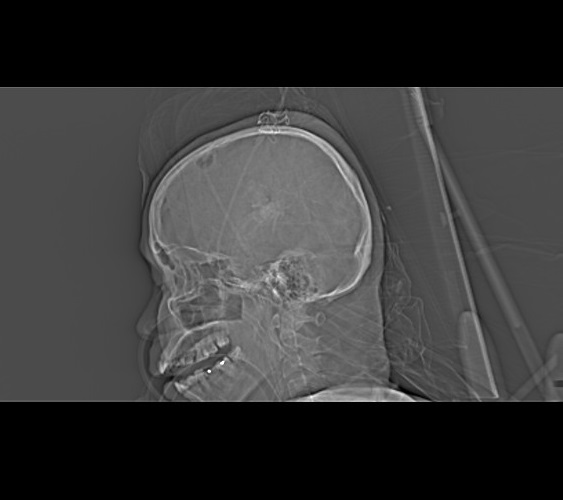

Topogram AP

Topogram Lateral

Topogram Parameters

Topogram (AP)

- Topogram length: 512Ā cm

- Slice: 0.6 mm

- Scanning direction: Craniocoudal

- Tube position: Top

- Stop the topogram scanning when the scanning reach / pass over the arch of aorta

Topogram (Lateral)

- Topogram length: 256Ā cm

- Tube position: Lateral

- Stop the topogram scanning when the scanning reach / pass over the base of skull